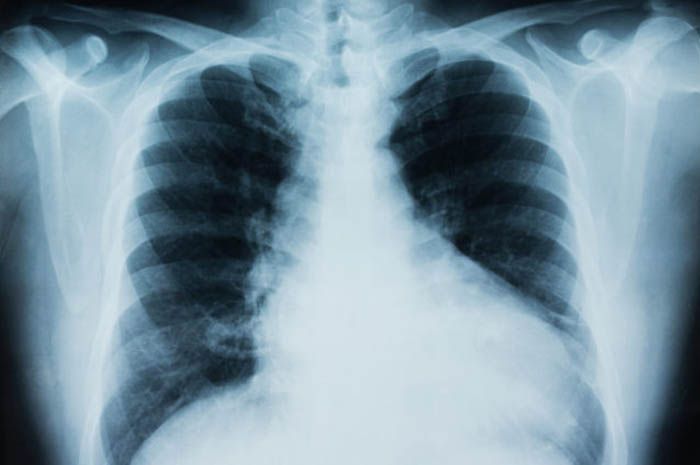

Ilustrasi Kanker Paru-paru